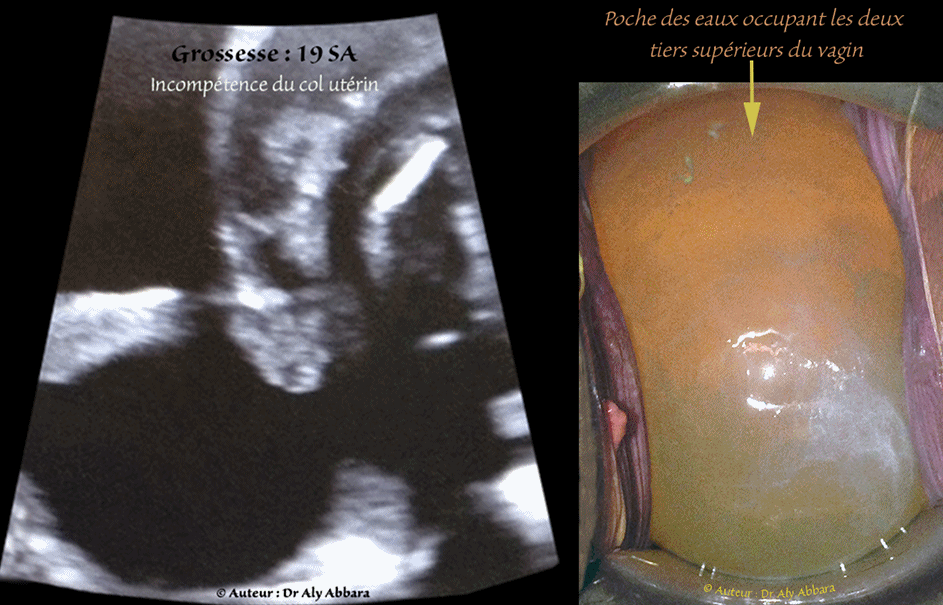

Série d'images montrant les aspects échographiques et cliniques d'un col utérin à orifice interne incompétent permettant la protrusion de la poche des eaux à travers le canal cervical afin d'occuper les deux tiers supérieurs du vagin (poche des eaux en forme de sablier).

Il s'agit d'une femme enceinte de 19 SA, primigeste, primipare avec une grossesse obtenue par FIV.

L'incompétence de l'orifice interne du col utérin fut découverte fortuitement lors d'une consultation prénatale urgente à 18,5 SA, pour des métrorragies minimes sans contractions ou douleurs abdomino-pelviennes ressenties par la patiente.

Le cerclage du col utérin à chaud paraissaint impossible car, en per-opératoire, la ré-introduction de la poche dans la cavité utérine à travers le col utérin a échoué. L'évolution de la grossesse a été marqué par la rupture précoce des membranes amniotiques à 19,5 SA puis l'avotement rapide dans la suite immédiate.